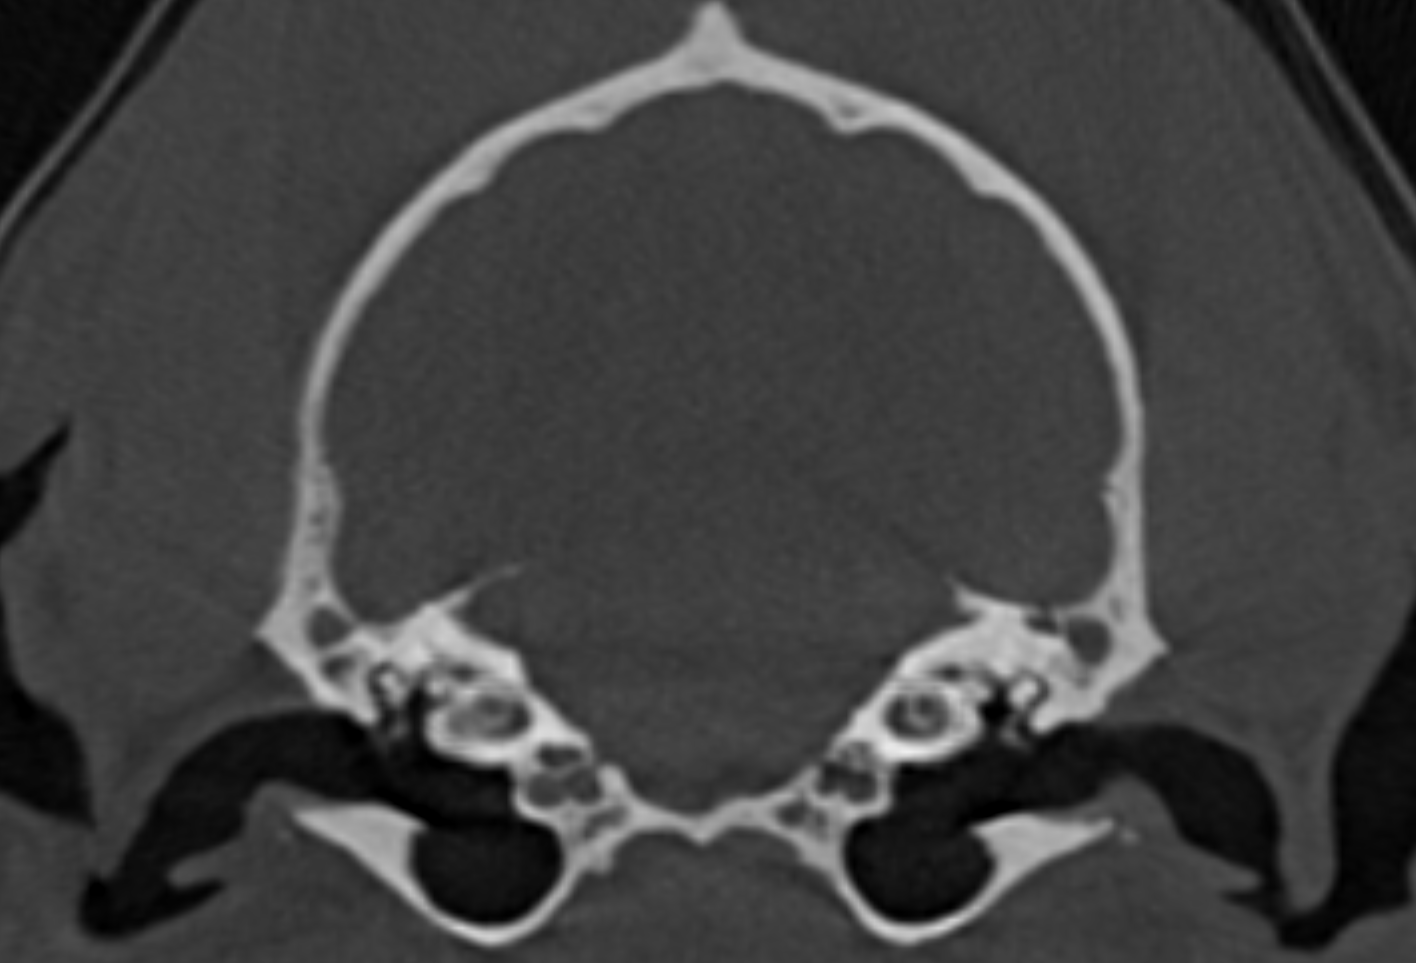

Die Computertomographie (CT) ist ein bildgebendes Verfahren, bei dem mithilfe von Röntgenstrahlen detaillierte Schnittsaufnahmen des Körpers erstellt werden. Sie ermöglicht die Darstellung innerer Strukturen in sehr hoher Detailgenauigkeit und unterstützt so die Diagnose und Kontrolle verschiedener Erkrankungen, beispielsweise im Bereich des Kopfes, des Brustkorbs, des Abdomens und der Extremitäten.